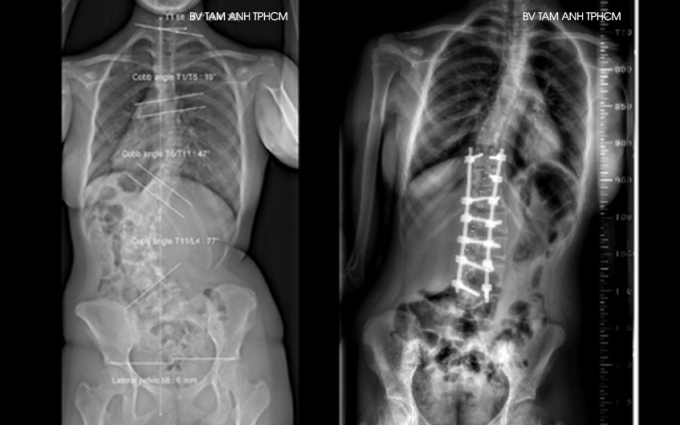

Phẫu thuật được chỉ định khi người bệnh không đáp ứng tất cả hướng điều trị nội khoa hoặc bệnh có chuyển biến nặng, cong vẹo cột sống hơn 40 độ. Bác sĩ loại bỏ các thành phần xương, đĩa đệm, dây chằng... bị hư tổn do cột sống cong vẹo gây chèn ép, sau đó nắn chỉnh lại cột sống về gần nhất có thể với đường cong sinh lý tự nhiên và cố định lại bằng móc, vít, thanh nẹp...

Tại Bệnh viện Đa khoa Tâm Anh, một ca phẫu thuật thường hơn 3 giờ với sự hỗ trợ của các máy móc như dao cắt xương siêu âm không gây tổn thương mô mềm và các cấu trúc thần kinh, C-Arm chụp X-quang liên tục trong lúc mổ để các vít, thanh nẹp cố định cột sống được đặt đúng vị trí; máy theo dõi chức năng tủy sống đảm bảo người bệnh không bị biến chứng thần kinh... Người bệnh có thể xuất viện sau 3-7 ngày. Tùy tốc độ liền xương, trẻ có thể chơi các môn thể thao nhẹ nhàng như bơi lội, đi bộ sau 3-6 tháng phẫu thuật, vận động mạnh sau 6-12 tháng.